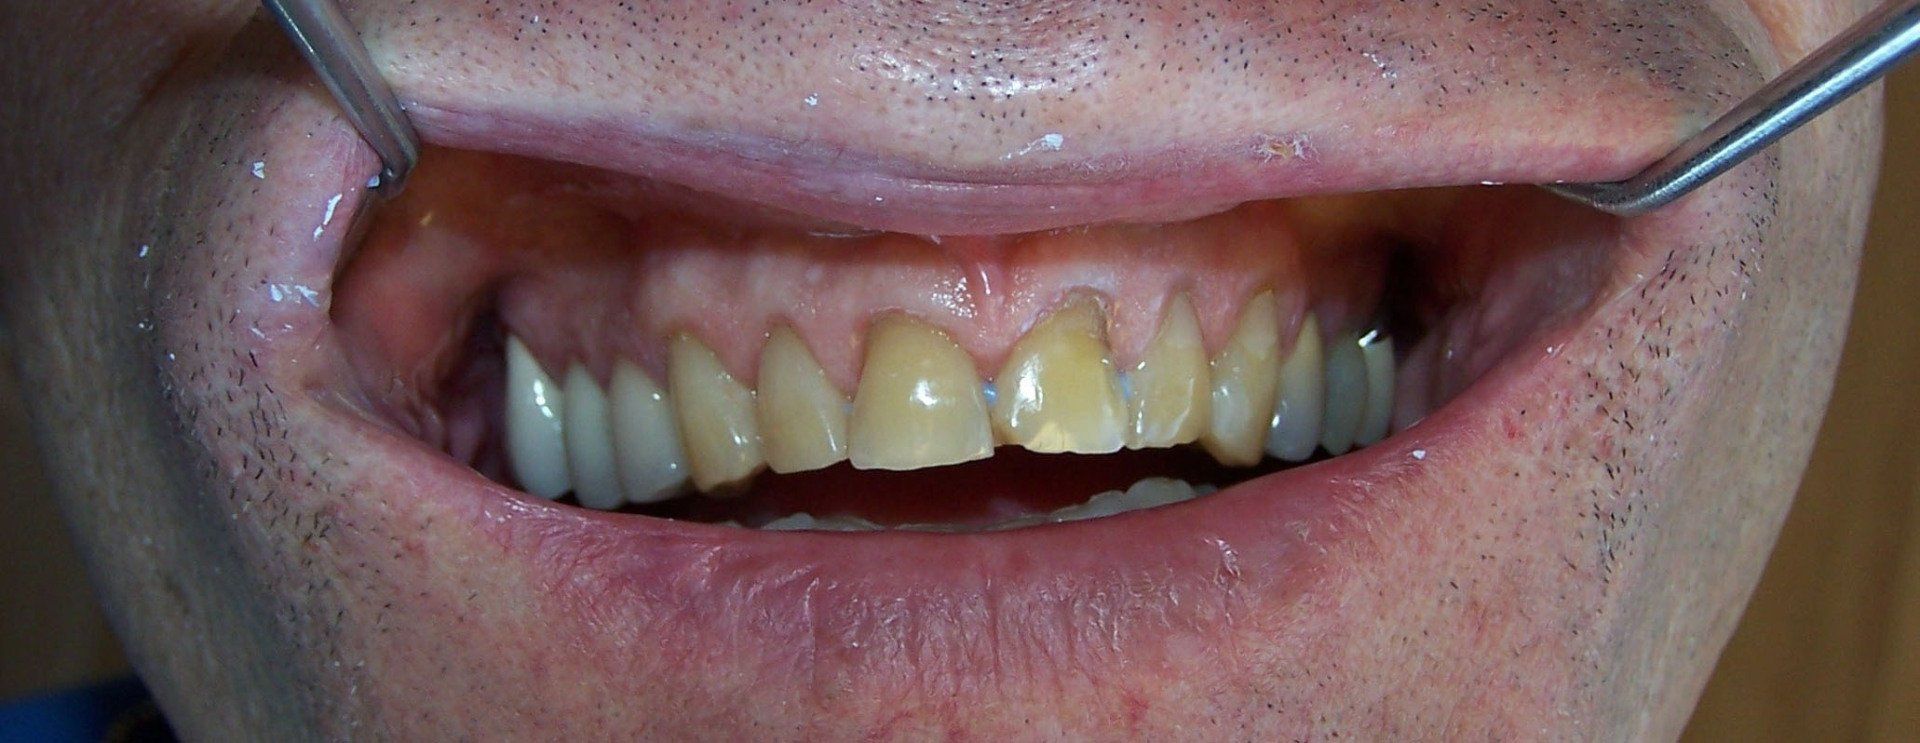

Ralph Before

Button

Ralph After